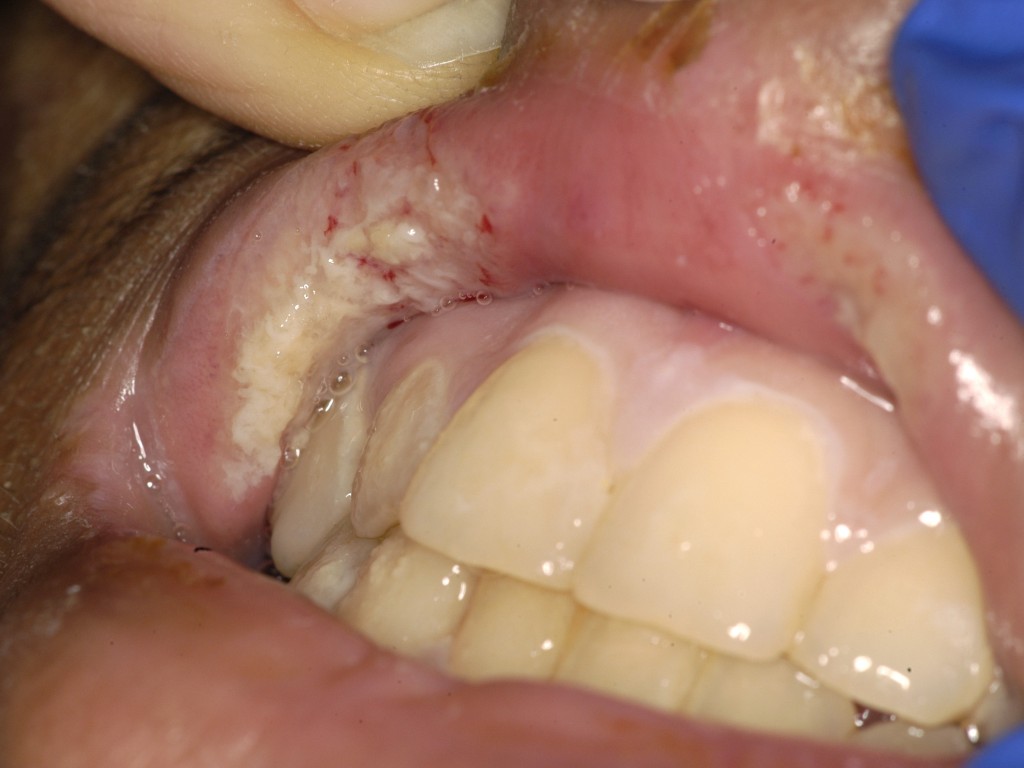

Pyostomatitis vegetans is een zeldzame afwijking van het mondslijmvlies bij

IBD, het wordt beschouwd als de orale variant van pyoderma vegetans. Er

ontstaat een ontsteking van het wangslijmvlies met multipele grijze of gele

pustels, die overgaan in erosies en ulceraties. Kan ook op de gingiva

zitten, verhemelte, en in de keel rond de tonsillen. De tong en de mondbodem

blijven meestal gespaard. Kan ook op andere slijmvliezen voorkomen (vagina,

neusslijmvlies, conjunctiva).

![Pyostomatitis vegetans (click on photo to enlarge) [source: www.huidziekten.nl] Pyostomatitis vegetans](../../../images/pyostomatitis-vegetans-1z.jpg) |

![Pyostomatitis vegetans (click on photo to enlarge) [source: www.huidziekten.nl] Pyostomatitis vegetans](../../../images/pyostomatitis-vegetans-2z.jpg) |

| pyostomatitis vegetans |

pyostomatitis vegetans |